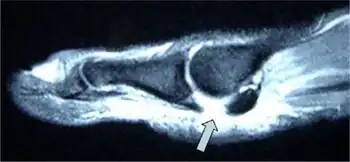

A metatarsophalangeal joint sprain is an injury to the connective tissue between the foot and a toe (at a metatarsophalangeal joint, one of the joints in the ball of the foot). When the big toe is involved, it is known as "turf toe".[1][2]

Diagnosis

In terms of the diagnosis of turf toe one finds that a clinical exam as well as x-rays are done[3]